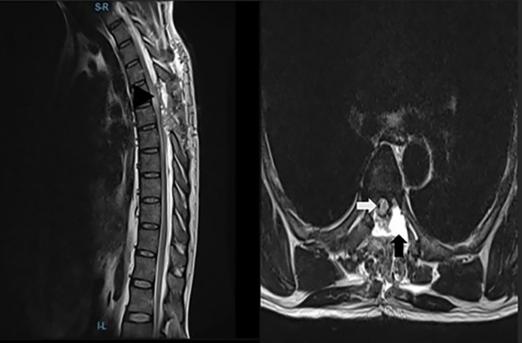

由于保险障碍和经济困难,患者无法获得恰当的影像学检查,直到症状出现3个月后,才到文章发表医院进行神经外科评估和护理。神经病学检查显示下肢力量为0/5,深部腱反射减少,和足底伸肌反应。感官等级为T6(轻触)。脊柱磁共振成像显示腹外侧硬膜内髓外囊性病变跨越T5-T6。囊肿占据了椎管横截面的50%以上(图1)。患者被诊断患有胸椎蛛网膜囊肿,美国脊柱损伤协会损伤分级为A级。接受了囊肿的手术切除,目的是提高从脊髓损伤中康复的机会。

图1、胸椎MRI矢状面(左)和轴面(右)显示腹侧囊性病变伴有严重脊髓压迫。黑色箭头表示蛛网膜囊肿,黑色箭头表示受压和移位的脊髓